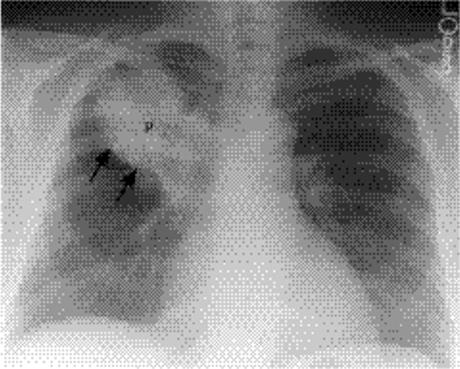

Figure 5.2 Opacity in pneumonia. (A) Posteroanterior and (B) lateral chest radiographs: vague retrocardiac abnormality (P) with corresponding increased opacity over the lower thoracic spine on the lateral view (arrows).

Cavitating consolidation (Figs. 5.13 and 5.14) suggests bacteria or fungi. S. aureus, Klebsiella, anaerobes, and Mycobacterium tuberculosiscommonly cause cavitation. Pneumatoceles may result in a similar appearance (Fig. 5.15) and suggest S. aureus or S. pneumoniae.Emphysematous bullae within consolidated lung may mimic cavities.

Figure 5.13 Cavitary pneumonia. (A) Posteroanterior, and (B) Lateral chest radiographs: cavity with a gas-fluid level (arrows) in the superior segment of the right lower lobe.